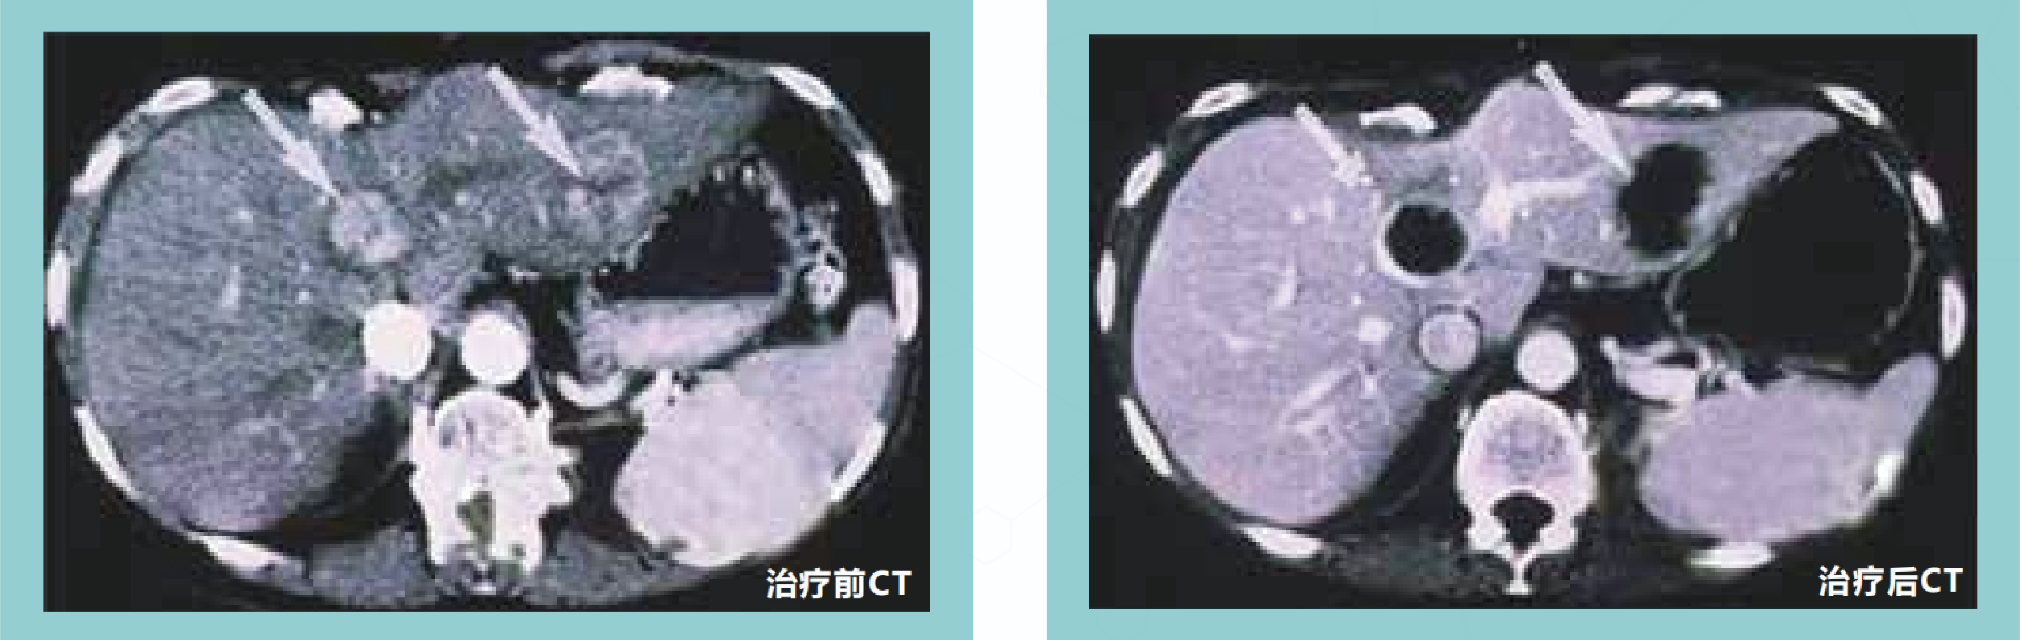

在超声或CT的引导下经皮穿刺肿瘤中心后,注射化学消融剂,直接作用于肿瘤组织蛋白,使癌细胞脱水固定,蛋白质凝固变性,破坏肿瘤细胞,凝固坏死组织可逐渐被吸收或瘢痕化,而周围组织无显著损伤。经皮化学消融治疗适...

在超声或CT的引导下经皮穿刺肿瘤中心后,注射化学消融剂,直接作用于肿瘤组织蛋白,使癌细胞脱水固定,蛋白质凝固变性,破坏肿瘤细胞,凝固坏死组织可逐渐被吸收或瘢痕化,而周围组织无显著损伤。

经皮化学消融治疗有效率

经皮化学消融治疗对直径小于2厘米的肝癌有效率为90%~100%,对直径3厘米左右的肝癌有效率为70%。